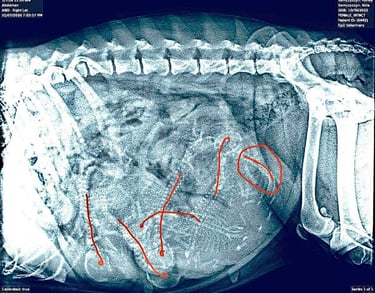

Update: 10 January 2026. Six puppies confirmed on X-Ray. We will be welcoming a new batch of Snarfs early next week.